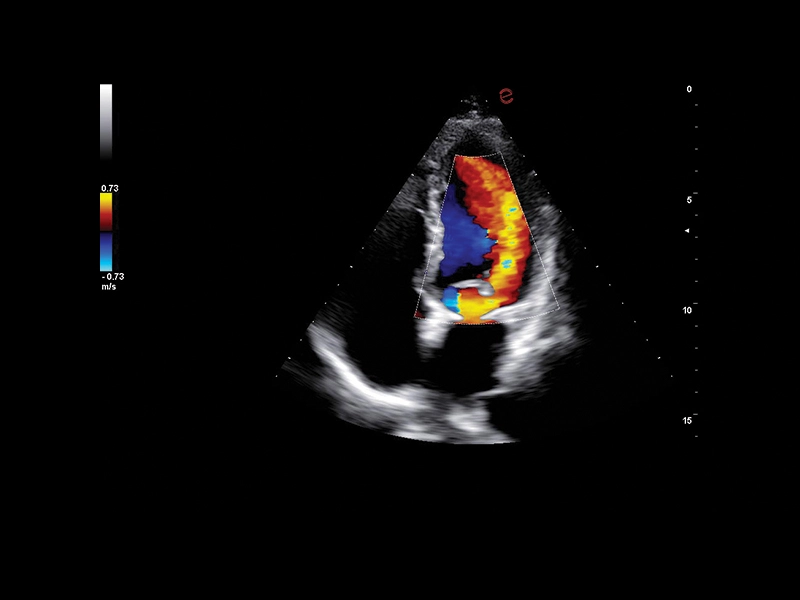

Q7 - Cardio CFM

Q7 - Cardio CFM

MyLab™A50 - Heart CFM

MyLab™A50 - Heart CFM

MyLab™A70 - Heart CFM

MyLab™A70 - Heart CFM